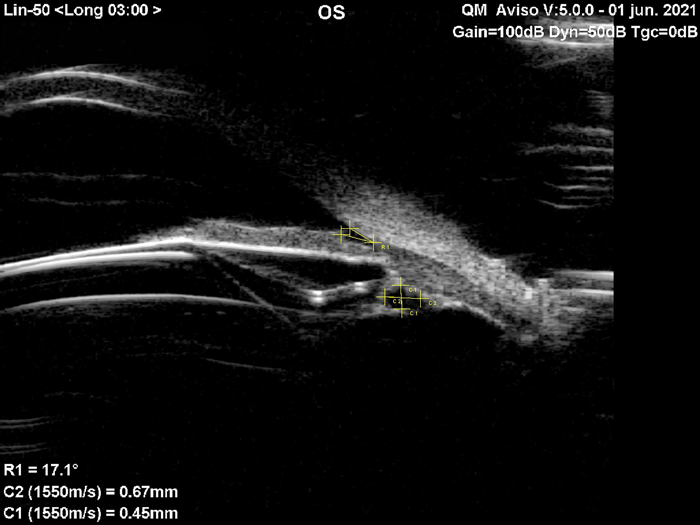

Existen casos como el que se observa en la imagen tomada con una UBM (Aviso®, Quantel Medical, Cournon-d’Auvergne, Francia) durante el control postoperatorio realizado al mes del implante, donde se detectó que el háptica de la lente quedó “descansando” sobre un quiste. En este caso, en el control preoperatorio se habían detectado quistes pequeños en los 360°. A partir de ello se le explicó la situación al paciente e igualmente se realizó la cirugía, pero se decidió colocar una medida de lente más pequeña que la recomendada, de acuerdo con el valor obtenido de la distancia blanco-blanco en la UBM. La lente implantada es una IPCL tórica, difractiva (Care Group, India). El vault obtenido fue de 750 micras y el paciente se mantiene estable sin complicaciones, con un seguimiento que en la actualidad es de seis años.

There are cases such as the one shown in the UBM image (AvisoTM, Quantel Medical; Cournon-d’Auvergne, France), during the postoperative control performed one month after implantation, where it was detected that the lens haptic was “resting” on a cyst. In this case, in the preoperative control, small cysts had been detected in the 360°, from which the situation was explained to the patient, and the surgery was still performed, but it was decided to place a smaller lens size than recommended according to the value obtained from the white-white distance in the UBM. The implanted lens is a toric, diffractive IPCL (Care Group, India). The vault obtained was 750 microns and the patient remains stable without complications, currently with a follow-up of six years.